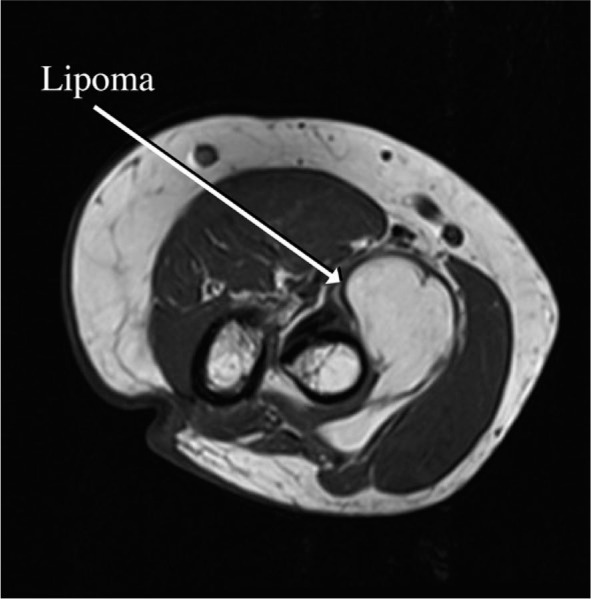

背景:骨间后神经损伤是一种罕见的上肢单神经病变。创伤性骨间后神经损伤通常由前臂脂肪瘤引起,表现为缓慢进展的腕关节和手指下垂:在本综述和病例报告研究中,我们对因脂肪瘤导致骨间后神经麻痹的患者和一例罕见的因脂肪瘤导致急性骨间后神经损伤的患者进行了系统的文献综述。我们主要关注的是临床表现的时间。在综述过程中,我们遵循了《系统综述和元分析首选报告项目》指南:在查阅文献后,我们确定了 30 例由脂肪瘤引起的后骨间神经损伤患者。28例患者的症状呈进行性发展,从1个月到最长240个月不等。我们只发现了一例急性发病的患者和另一例因外伤导致慢性无力急性恶化的患者:结论:创伤性骨间后神经损伤经常继发于前臂脂肪瘤。在大多数病例中,症状会逐渐发展。然而,在本研究中,我们也报告了一例罕见的因脂肪瘤导致急性后骨间神经损伤的患者。

Background: Posterior interosseous nerve lesion is a rare mononeuropathy of the upper limb. Atraumatic posterior interosseous nerve lesions are commonly caused by lipomas of the forearm, manifesting as slow-progressing wrist and finger drop.

Results: After reviewing the literature, we identified thirty patients with posterior interosseous nerve lesions caused by lipomas. In 28 patients, the symptoms presented progressively, ranging from 1 month to a maximum of 240 months. We found only one case of a patient with acute presentation and another patient with acute worsening of chronic weakness due to trauma.

Conclusions: Atraumatic posterior interosseous nerve lesions are frequently secondary to forearm lipomas. In the majority of cases, the symptoms will develope progressively. However, in this study, we also report a rare case of a patient presenting with acute posterior interosseous nerve lesion due to a lipoma.